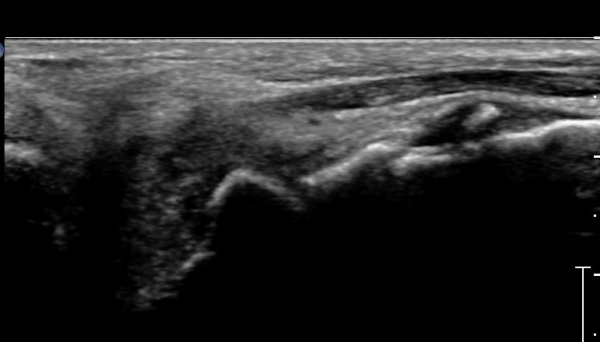

¹ß¸ñ ÇϺνÅÀüÁöÁö¶ì(inferior extensor retinaculum)ÀÇ frondiform Àδë Á¾´Ü¸é°Ë»ç ¹× Á·±Ùµ¿

Ⱦ´Ü¸é°Ë»ç¿¡¼­ °Å°ñ °æºÎ ¿ÜÃø °ß¿­°ñÀý, frondiformÀÎ´ë ½ÉÃþ ¼Õ»ó, ±×¸®°í Á·±Ùµ¿ °æºÎÀδë

(cervical ligament) ÆÄ¿­ÀÌ ÃßÁ¤µÈ´Ù(»çÁø 4, 5).